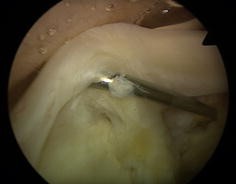

Fig. 2